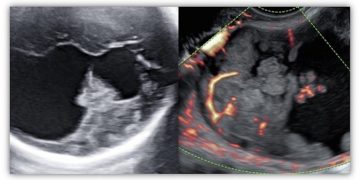

Caso del Mese di Dicembre 2021

Cari soci, finalmente la soluzione del caso del mese di Dicembre! Scarica il File L'attesa è finita: Al seguente link la...